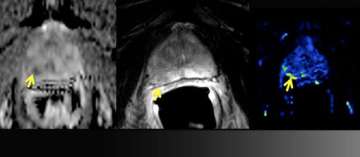

6) Dynamic Contrast-Enhancement for Biochemical Failure

Dynamic Contrast-Enhancement for Biochemical Failure